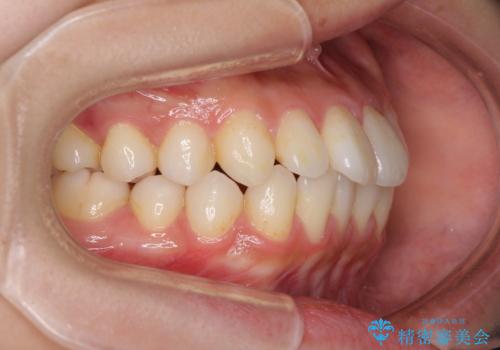

インビザラインで口を閉じやすく

- 下唇に上の前歯が当たることを気にして来院された患者様です。

上顎の親知らずを抜去し、歯列全体を後方に移動させるとともに、IPR(歯と歯の間を削る)を行うことで口元の閉じにくさを改善していくこととしました。

咬合力が強く、マウスピースを介した咬み込みが顕著であったため、奥歯の咬みにくさやIPRのスペースが改善しにくく、治療期間が思った以上にかかってしまいました。